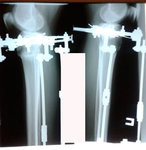

Пациентка - 37 лет.

Дата операции - 24.10.2019г.

Диагноз: варусная деформация голеней. Ротация с обеих сторон.